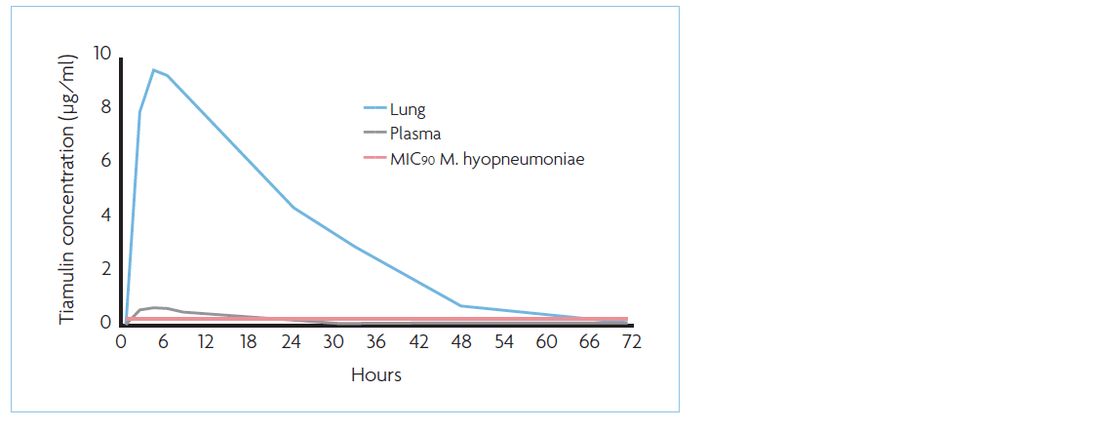

The minimal inhibitory concentration of tiamulin to inhibit growth of 90% (MIC90) of the M. hyopneumoniae strains tested is not more than 0.06μg/ml (Table 1).

This molecule does not only show an excellent absorption after oral administration and a low plasma protein binding capacity but also high tissue concentrations in the lung. The exposure to tiamulin is 18 times higher in lung tissue compared to plasma (Figure 2).